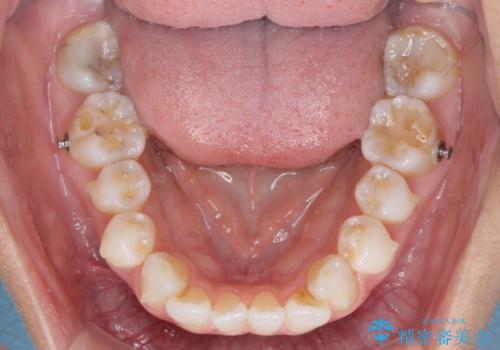

- 少しだけ前に飛び出ている前歯を気にして来院された患者様です。

上顎歯列全体を後方に移動させる必要があり、インビザライン単体での治療は困難と判断し、補助装置により左右側方歯列を移動させた後にインビザラインを用いることとしました。